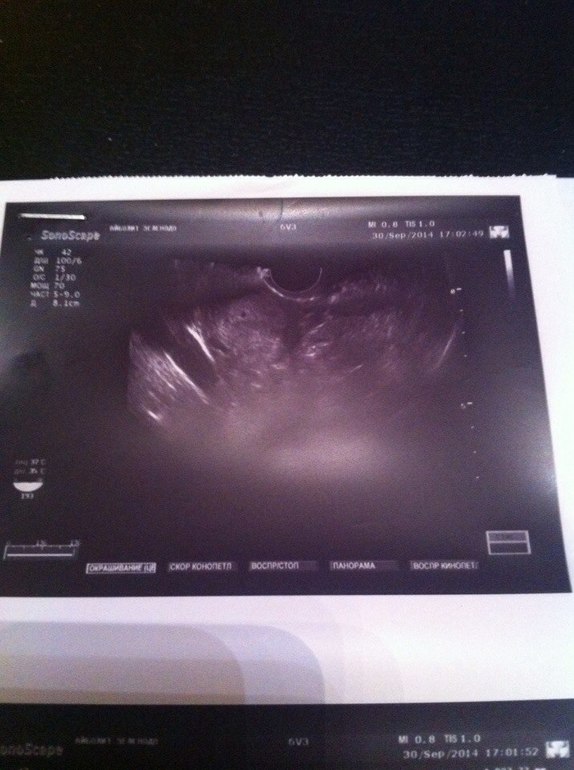

ФолликулометрияНачну с начала... сегодня ныл. болел как мне казалось левый яичник. Написала в ББ, многие посоветовали бежать на УЗИ. У меня или 16 или 17 дпо, я уже запуталась как считать=)вчера тест показал яркую вторую полоску... Пошла на узи... сначала гинеколог сказала что ничего не видит, я разревелась прям на кушетке... Потом посмотрела через живот и по прежнему ничего не увидела=((( потом решила повторить вагинальное узи,видимо видя мое состояние, и увидела там маленькую точечку в 1.8 мм... Переживаю страшно=((( на фото вроде бы видно, но что-то уж совсем маленькая точечка... Это нормально? Кто понимает в этом или у кого так было напишите пожалуйста... Завтра иду сдавать Хгч

поздняя О была? у меня посл мес были 25 авг (начало) сегодня 20 ДПО...если 15 ДПО то 2 недели от зачатия только!!!Диаметр плодного яйца в 2 мм соответствует сроку беременности менее 4-х недель, к 5-ти неделям, диаметр плодного яйца должен достигать 5 мм.Просто срок маленький очень, из-за поздней О

У Вас хороший размер желтого тела! Если бы ожидались месячные, оно бы уже пошло в регрессию. Так что, не переживайте, я думаю,Ваша беременность подтвердится по анализу хгч и на повторном узи. Тихо-тихо поздравляю и прошу самый заразный чих

а мне не очент нравится размер жт для беременности бы побольше ...но с дюфом все лучше пойдет.. даже если тьфу тьфу была внематочная то на таком сроке она не болит...хотя в четверг мне тоже узи сделают но это у моего репродуктолога такой прием включ узи...аппарат в кабинете стоит ))и вообще не парься нашли точку в матке успокойся и кайфуй)